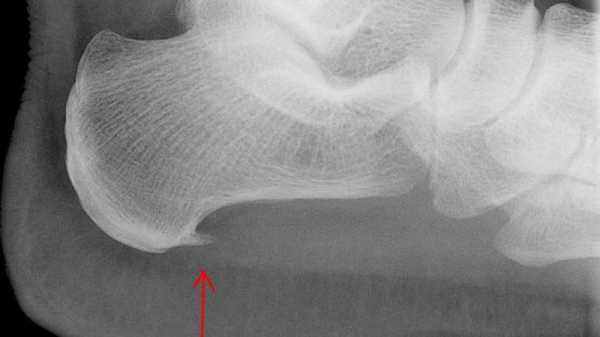

Пяточная шпора на рентгеновском снимке